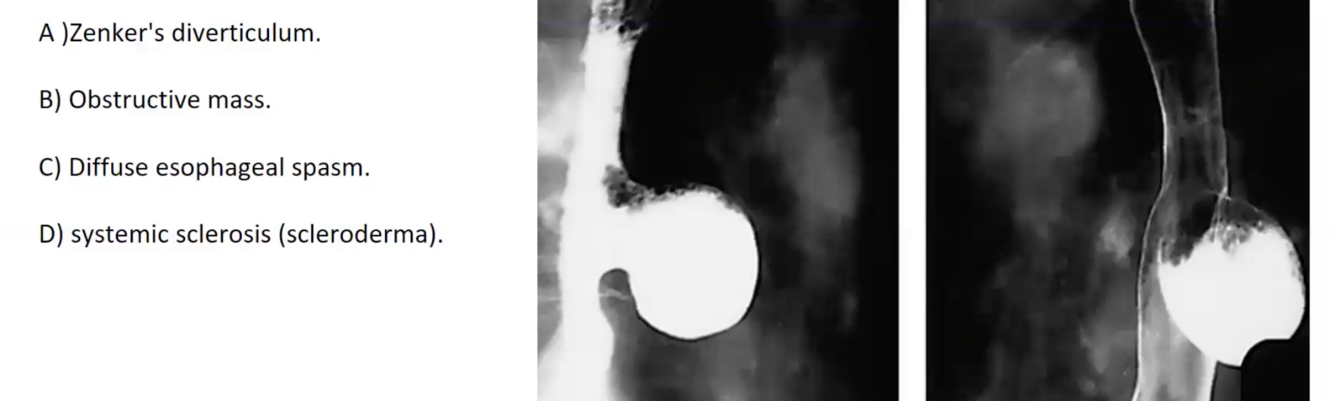

OUTPOUCHING ZENKERS

OBSTRUCTIVE MASS

ESCLERODERMIA

DIFFUSE ESOPHAGEAL